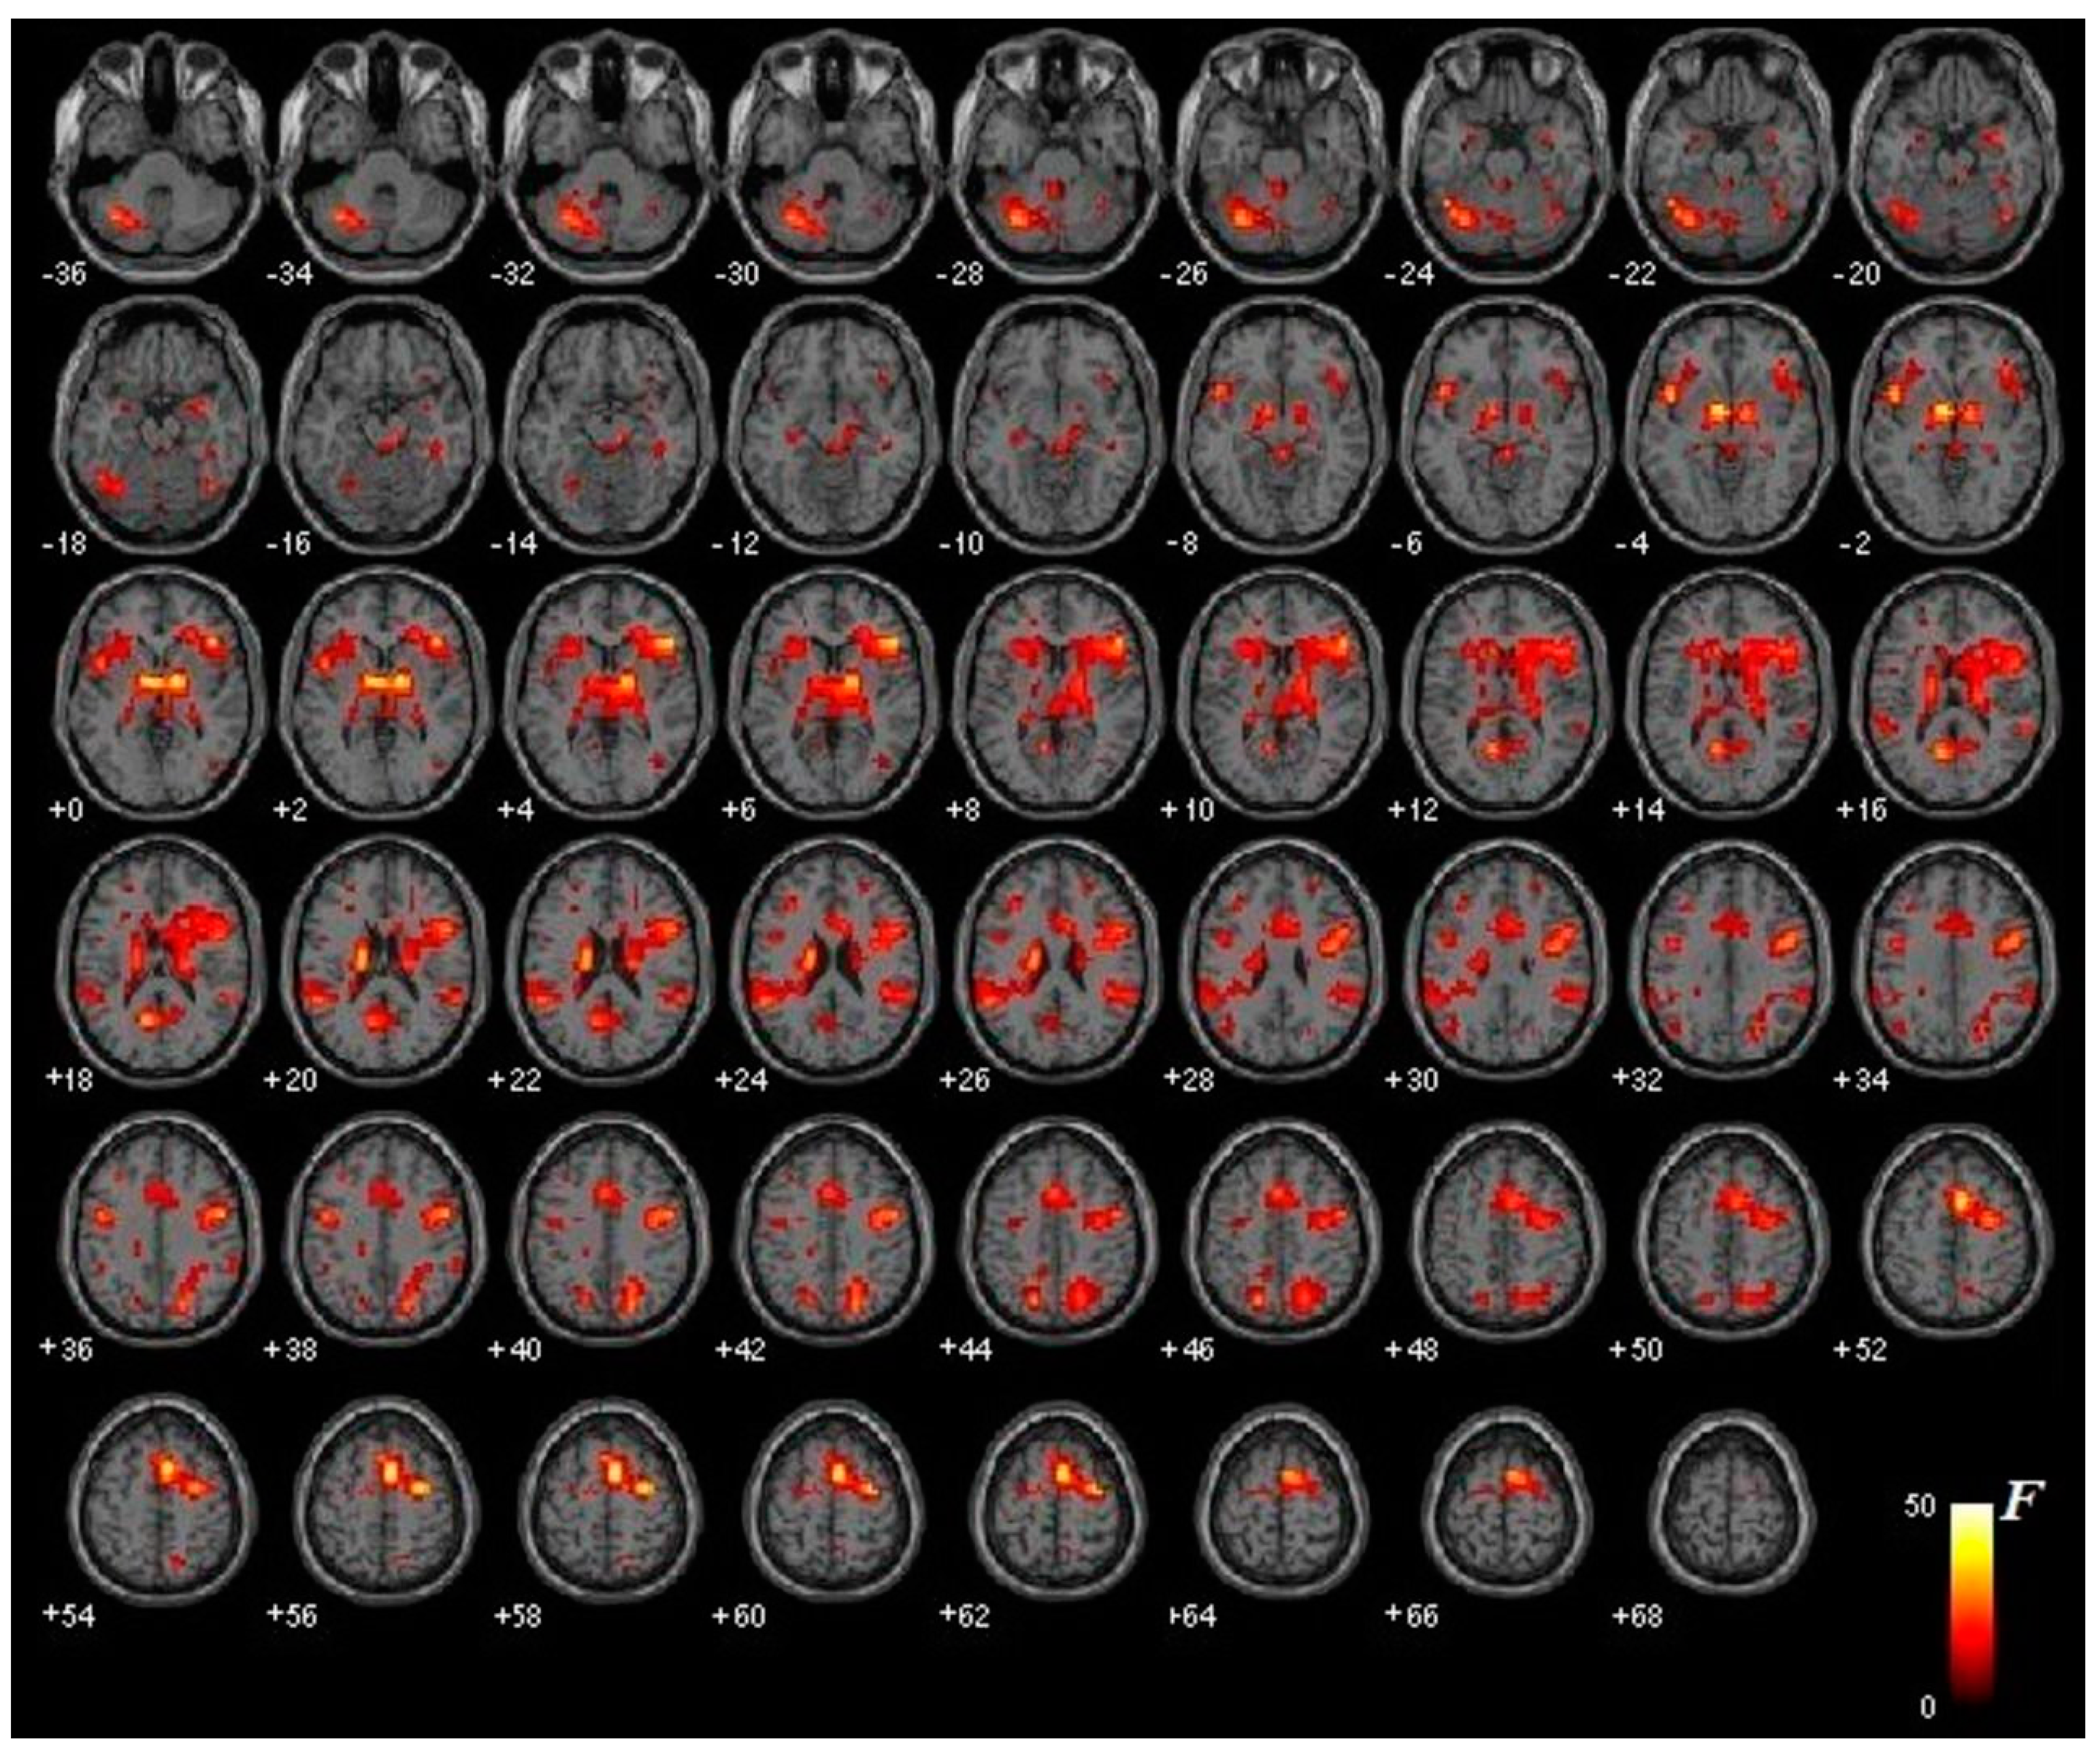

3.2. Functional Brain Activation